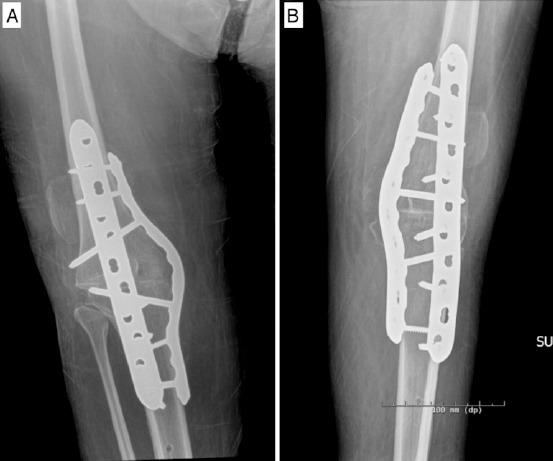

A 47-year-old man presented with bilateral hip and knee pain. Radiographs demonstrated valgus knee deformities with severe arthrosis and bilateral femoral head subluxation. The patient had a history of spina bifida with chronic lower extremity weakness and neurogenic bladder. He underwent staged bilateral instrumented knee arthrodesis and staged bilateral total hip arthroplasty (THA).

一名47岁男性因双侧髋部和膝部疼痛就诊。X线片显示膝外翻畸形伴严重关节炎和双侧股骨头半脱位。该患者有脊柱裂病史,伴有慢性下肢无力和神经源性膀胱。他接受了分期双侧器械辅助膝关节融合术和分期双侧全髋关节置换术(THA)。

这是首例报道的脊柱裂患者接受双侧器械辅助膝关节融合术的病例。这些患者的骨科护理较为复杂。通过器械辅助关节融合术和全髋关节置换术对有症状的膝部和髋部畸形进行手术矫正,可能会改善功能结局。